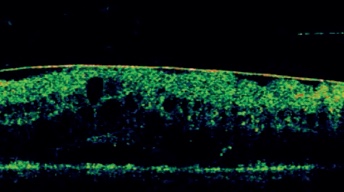

Qué nos muestra en la retinopatía diabética

Permite identificar:

Edema macular difuso o quístico.

Desprendimiento seroso del neuroepitelio.

Exudados duros reflejantes.

Tracción vítreo-macular o membrana epirretiniana.

Evalúa la respuesta al tratamiento con antiangiogénicos o láser.